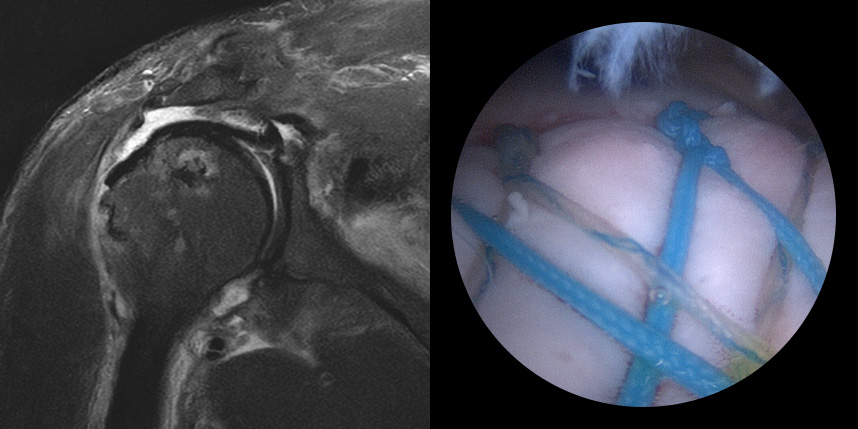

브릿지 봉합술

접촉면접과 힘줄

부착 압력이 높습니다.

초기,중기,말기 파열에

주로 사용됩니다.

상대적으로

재파열율이 낮습니다.

* 환자에게 받은 소중한 자료입니다.